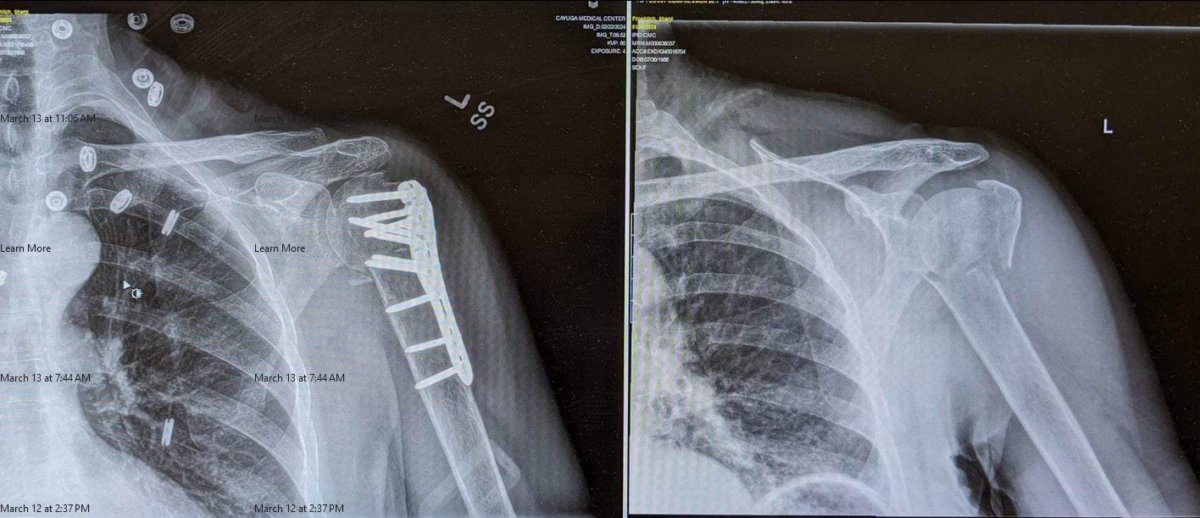

Sheryl here.  Today I am 80 days post proximal humerus fracture in 3 places and mark 10 weeks post ORIF  (Open Reduction Displacement Fixation)/biceps tenodesis surgery.   My fractured, displaced, comminuted (bone broken into 3 or more pieces) humerus now held together with a plate and 12 screws was X-rayed again yesterday and the surgeon confirmed the plate was holding its intended position and the bone is healing.  Furthermore, my nearly 7 inch surgical incision has closed without complication and after 8 weeks of physical therapy I am steadily regaining functional ROM (range of motion).  A few days ago I resumed driving (by myself - Steve was suddenly "busy"), and as of yesterday I can lift up to 4 cans of pumpkin pie filling (that's 5 pounds or 2.3 kg) with my left arm. I can absolutely measure progress.  And yet with all these gains, I am nowhere near anything approximating ‘normal.’